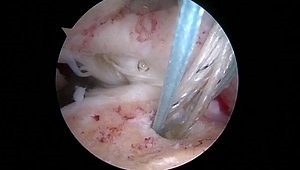

• Rotator Cuff Specialists | Cleveland Shoulder Surgeons

Types: Shoulder Replacement, Physical Therapy, Rotator Cuff Repair